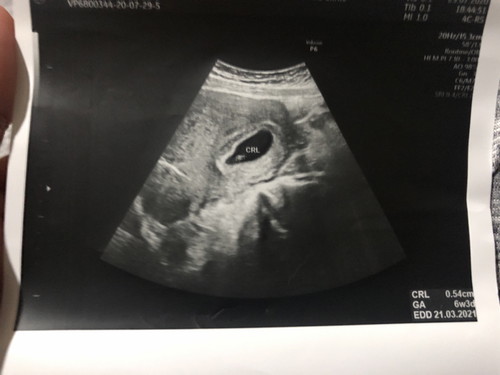

ท้องแรก ประจำเดือนวันแรกของเดือนที่มาเดือนสุดท้ายคือ วันที่ 11 พฤษภาคม 2563 ถ้านับอายุครรภ์ตามที่เข้าผ่านแอปนี้คือ อายุครรภ์ได้ 11 W+1 แต่ก่อนหน้านี้ไม่เคยไปฝากท้องที่ไหนเลย เมื่อวันอังคารที่ 21/7/63 เตรียมตัวไปฝากกับคลีนิค1 หมอแค่ตรวจความดัน และคล่ำๆหน้าท้อง ไม่ได้พูดอะไร ให้ยามาทานบำรุงปกติ และนัดมาตรวจเลือดอีกครั้งเดือนหน้า สิงหาเลย แต่ตัวเราเองไม่สบายใจอยากซาวด์ดูว่าน้องเป็นยังไง ปกติดีไหม เลยไปหาหมออีกคลีนิคที่ 2 เพื่อซาวดู แจ้งคุณหมอปกติว่ามีการขาดประจำเดือนเมื่อไรยังไง คุณหมอก็นับครรภ์ตรงกับที่ในแอปนี้บอก 11 W+1 ใช้เครื่องซาวด์ พบถุงการตั้งครรภ์อยู่ในหมดลูกปกติ แต่ในนั้นไม่มีตัวเด็ก คือใจเสียมาก (ก่อนหน้านี้ดีใจและมีความหวังและตั้งใจจะมีน้องมาตลอด)😭 ไม่มีการเต้นของหัวใจ จากที่เคยอ่านๆเรื่องราวคนอื่นคือจะเห็นตัวทารกใน 8 สัปดาห์ 😭 คุณหมอแจ้งว่าให้นัดไปดูดถุงการตั้งครรภ์ออก แต่ทางเรากับแฟนก็เลือกที่จะปรึกษากันก่อนว่ายังไง เพราะเราคิดว่ายังมีหวังอยู่ เลยถามคนใกล้ชิดว่าหมอไหนซาวด์และให้คำแนะนำดีบ้าง เลยให้ญาติพาไปอีกคลีนิคที่ 2 ครั้งนี้รู้สึกชื่นใจขึ้นมาหน่อยแต่ก็ยังกังวน คุณหมอซาวพบตัวเด็กในถุงการตั้งครรภ์ แต่ตัวเด็กนั้นตัวเล็กมากๆ ผิดปกติกับถุงการตั้งครรภ์ที่มีขนาดใหญ่ ทางเราก็แจ้งประจำเดือนเหมือนที่แจ้งกับหมอคนแรก แต่วัดขนาดจากตัวทารกแล้ว ได้ประมาณ 6 W+3 รึเราอาจคำนวนผิดไป แต่ก็ยังมีเรื่องกังวนคือไม่มีการเต้นตัวใจของตัวทารก (แม่เครียดอีกแล้ว) 😭 คุณหมอแนะนำว่าให้รออีก 2 อาทิตย์ถ้ายังไม่พบทารกแสดงว่าท้องลม ให้รีบทำการเอาออก แต่ทางเราคิดอีกว่าอยากไปตรวจอีกคลีนิคที่ 3 ให้หมั่นใจว่ายังไง ใครทราบหรือเคยมีประสบการณ์ด้านนี้แนะนำหน่อยค่ะ คือเครียดกังวนมาก ร้องไห้ตลอดเลย 😭😭🙏🙏